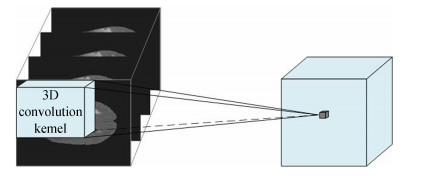

三维卷积神经网络与二维卷积神经网络原理类似,不同之处在于:三维卷积神经网络是在三维数据上进行卷积操作,卷积核及网络数据输出的数据均为三维格式.三维卷积的示意图如图 4所示.

图 4 三维卷积示意图